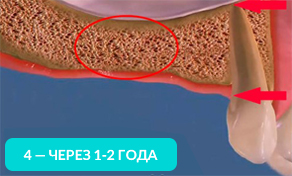

Как говорилось ранее, из-за отсутствия зубов, начинает происходить убыль костной ткани и её толщины может не хватить, чтобы установить имплант.

На 4-ом рисунке видно, что костная ткань стала значительно тоньше, теперь в это место уже невозможно установить импланты (потребуется операция по наращиванию костной ткани).

Обратите внимание, насколько тоньше стала кость на рисунке 4, как постепенно обнажается корень оставшегося зуба.

Убыль костной ткани распространяется на соседние зубы и их корни постепенно обнажаются!

Зубы, расположенные рядом с местом удаления, со временем становятся нестабильными и могут быть утрачены.